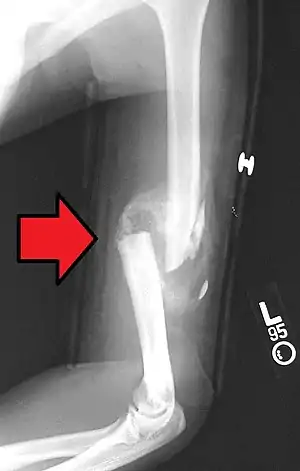

Bone healing of a fracture by forming a callus as shown by X-ray.

Bone healing, or fracture healing, is a proliferative physiological process in which the body facilitates the repair of a bone fracture.